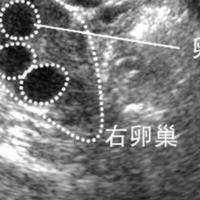

右侧卵泡怀孕必生男孩吗?科学揭开胎儿性别之谜

在民间说法和网络传言中,一直流传着"右侧卵泡排卵后怀孕就会生男孩"的观点,这一说法常被不少备孕家庭津津乐道,甚至有人刻意通过监测排卵侧来试图选择胎儿性别。然而,从现代生殖医学和生物学的角度来看,这种关联缺乏严谨的科学依据,更多是基于偶然概率或传统经验的过度解读。胎儿的性别本质上是由遗传物质决定的,而非母体排卵的左侧或右侧位置。右侧卵泡怀孕无法判断胎儿性别卵泡只是卵子的&quot...